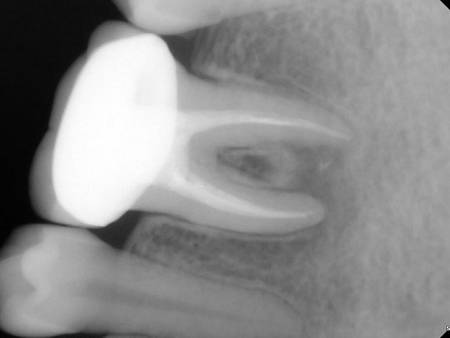

Root Canal Treatment Solution

Untuk setiap kondisi masalah gigi kamu, selalu ada solusi terbaik.

Penanganan yang tepat dengan alat dan teknologi yang memadai menjadikan hasil yang optimal